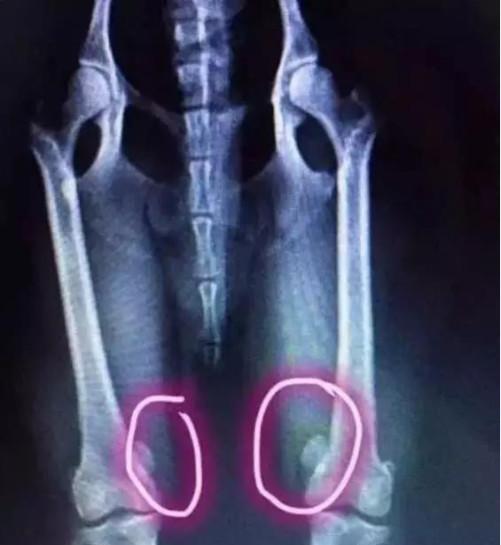

我家小泰迪腰椎给撞断了,做了手术。术后怎么